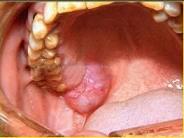

- 单项选择题以下关于黏液表皮样癌(如图)的叙述中,哪项是错误的 ( )

A、女性多于男性,发生于腮腺者居多

B、高分化黏液表皮样癌很少发生颈淋巴结转移

C、低分化黏液表皮样癌淋巴结转移率高

D、高分化和低分化者均应作选择性颈清

E、高分化黏液表皮样癌较低分化黏液表皮样癌常见